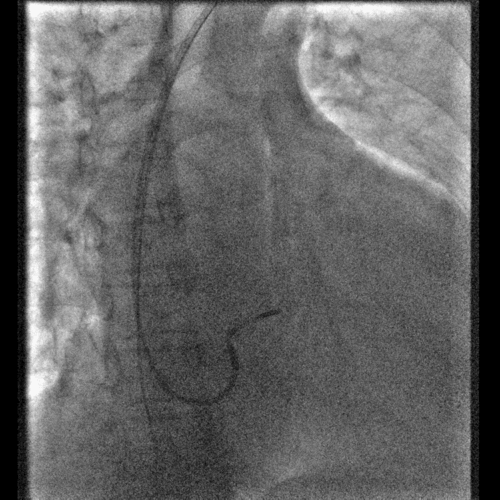

鞘中鞘的使用

果断选择鞘中鞘进入静脉分支,既能顺利通过扭曲,又能给电极提供更好的支撑力

美敦力的左室导线完美兼容鞘中鞘,提高植入成功率